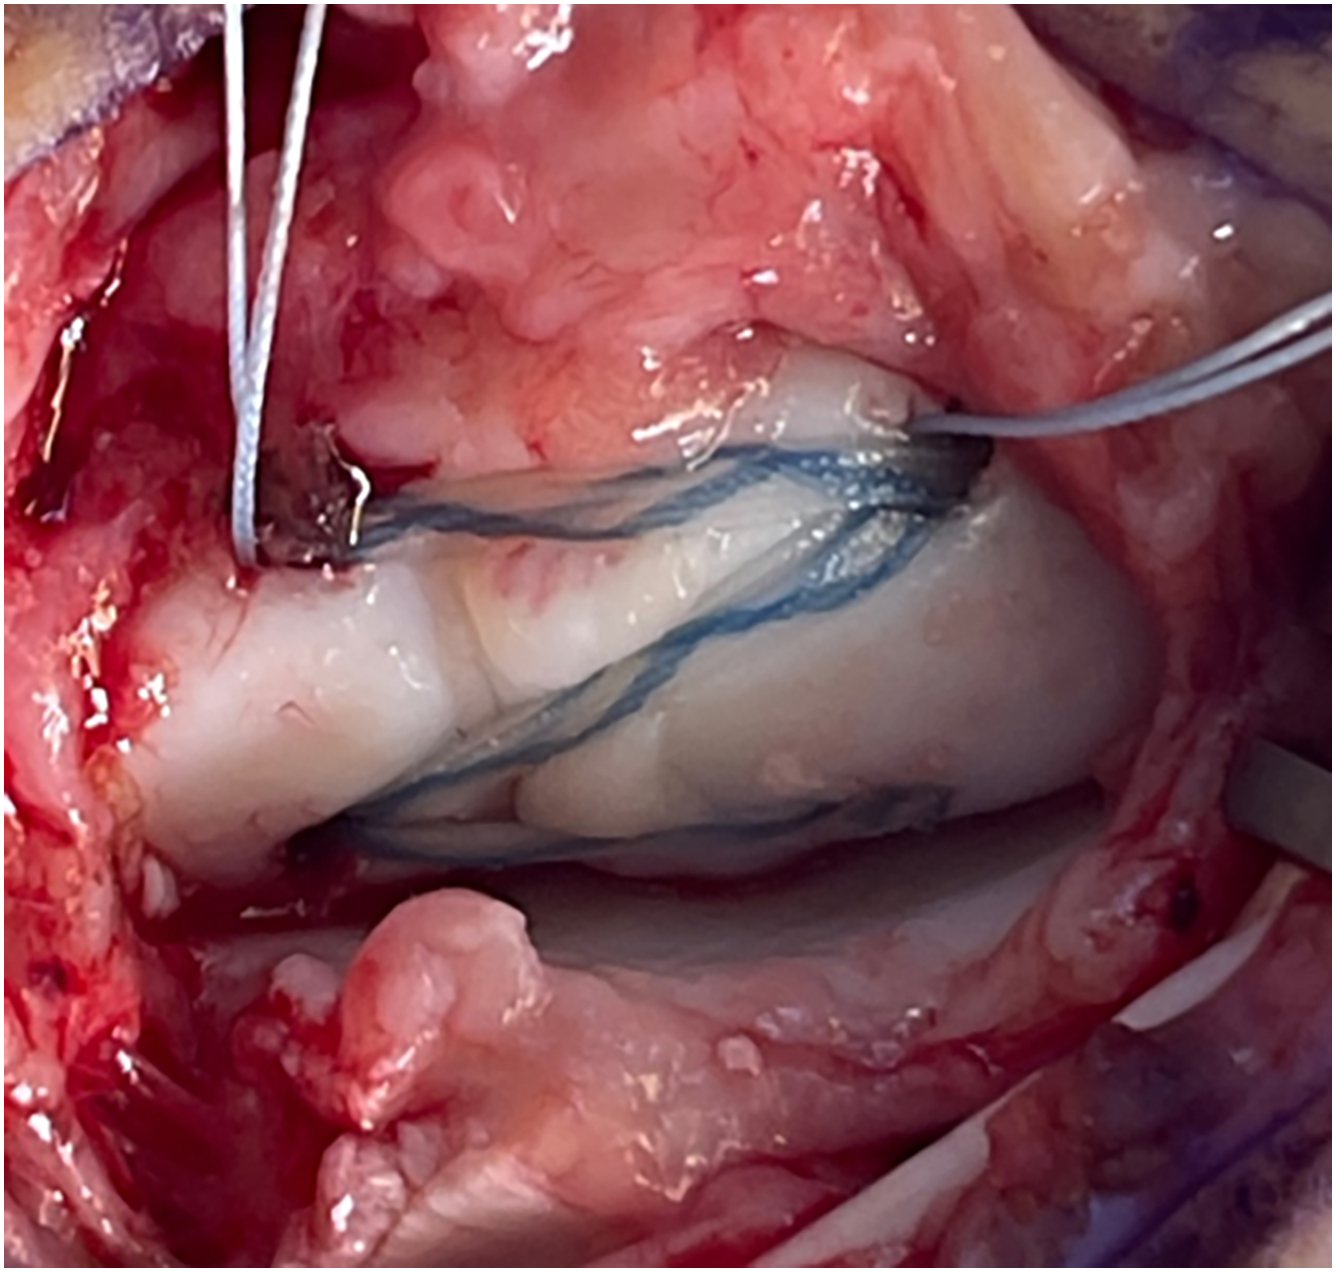

Numerous treatment options for SLIL injuries have been described and are guided by the degree (partial vs complete) and chronicity of injury. Partial tears are initially treated with a period of immobilization, anti-inflammatory medications, and/or cortisone injections. Those who continue to have symptoms may undergo arthroscopic evaluation with possible debridement and thermal shrinkage. For complete tears, open repair or reconstruction may be considered. Though many techniques for this have been described, our preference is internal brace reconstruction with dorsal capsulodesis ( Figs. 3 and 4 A, B ).